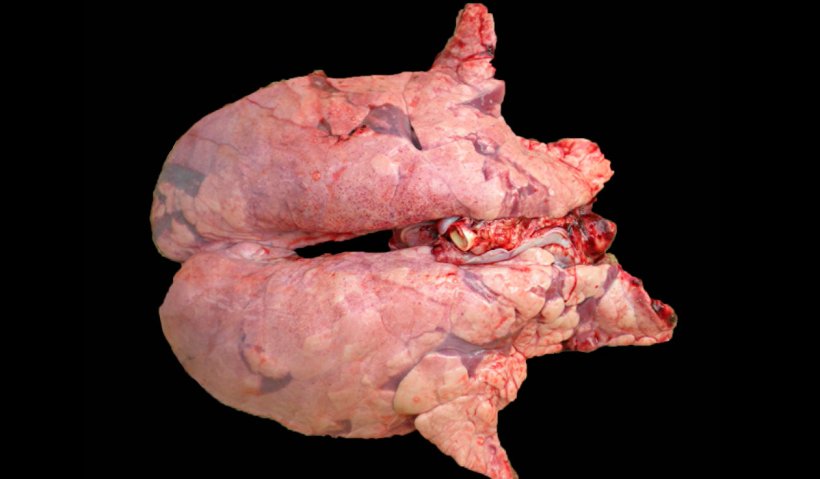

Hình 2. Phổi heo đồng nhiễm M. hyopneumoniae and virus PRRS. Phổi không bị xẹp với các vùng bệnh tích màu nâu đỏ rải rác khắp nhu mô, các bệnh tích điển hình của PRRS, đồng thời có các vùng nhục hóa màu đỏ ở phần rìa phổi, do nhiễm M. hyopneumoniae.